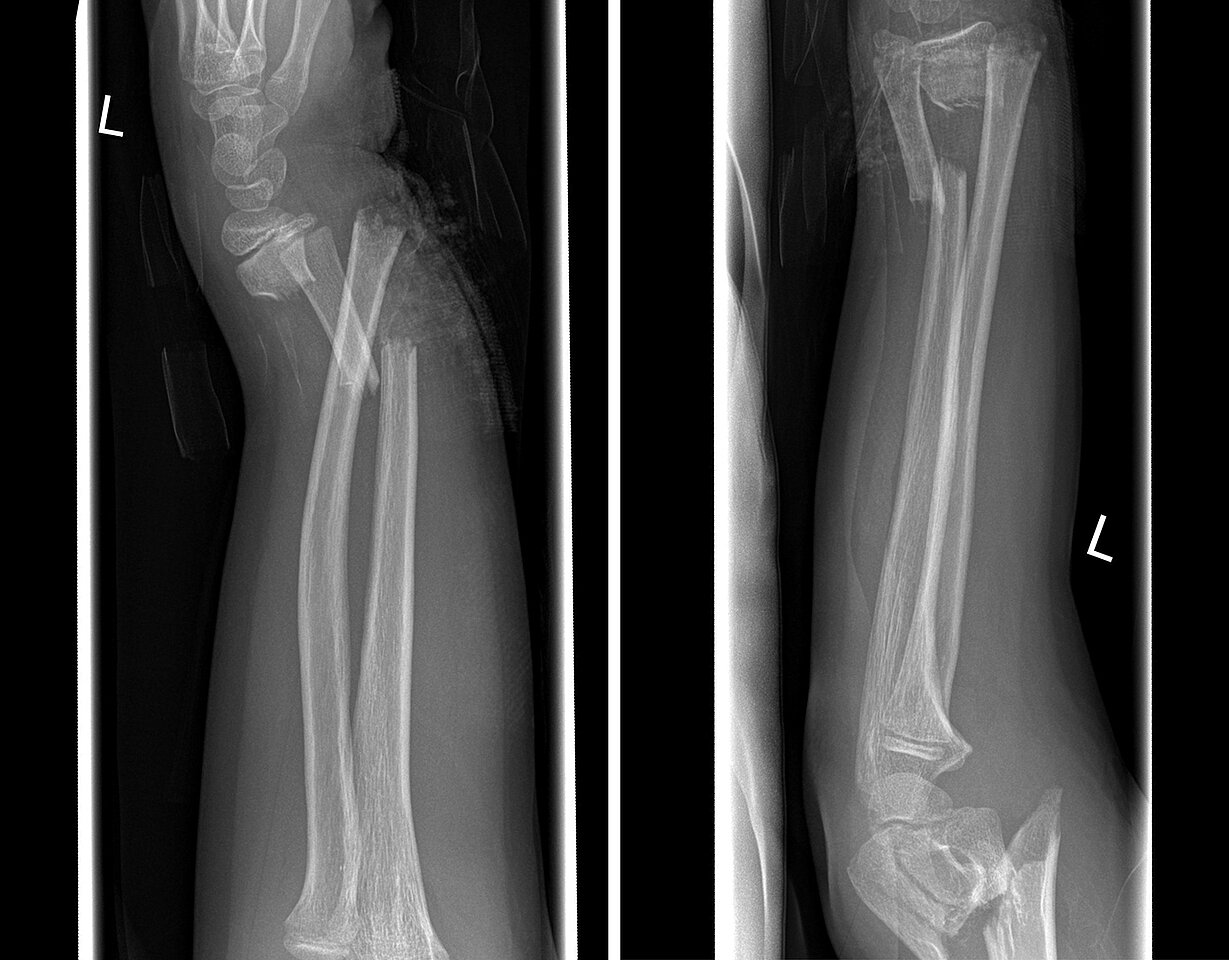

Schwere Unfälle treten nach seinen Angaben auch dann auf, wenn das Netz um das Trampolin nicht geschlossen oder defekt ist. In dieser Situation sind gravierende Verletzungen im Bereich des Ellenbogengelenkes oder des unteren Unterarms keine Seltenheit.